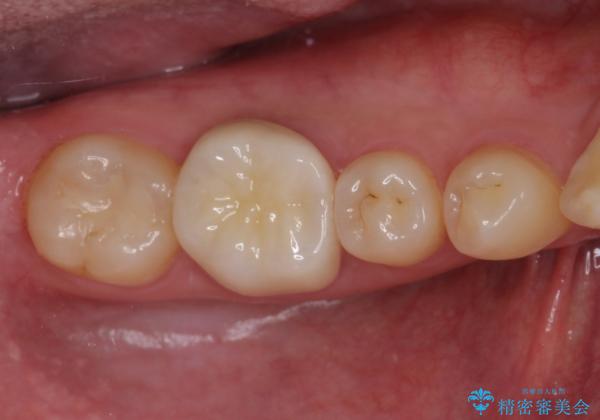

奥歯の目立つ銀歯が気になる 奥歯のセラミッククラウン

- 口を開けたときに目立ってしまう銀歯をセラミックに替えたいとのことで来院された患者様です。

以前むし歯治療を受けたときは時間がなかったため、近医で銀歯を入れたようですが、周囲の目線が気になるとのことでフルジルコニアクラウンにて補綴することとしました。

長年気にしていた銀歯を自然な色合いのセラミッククラウンに仕上げることができ、患者様には大変満足していただきました。